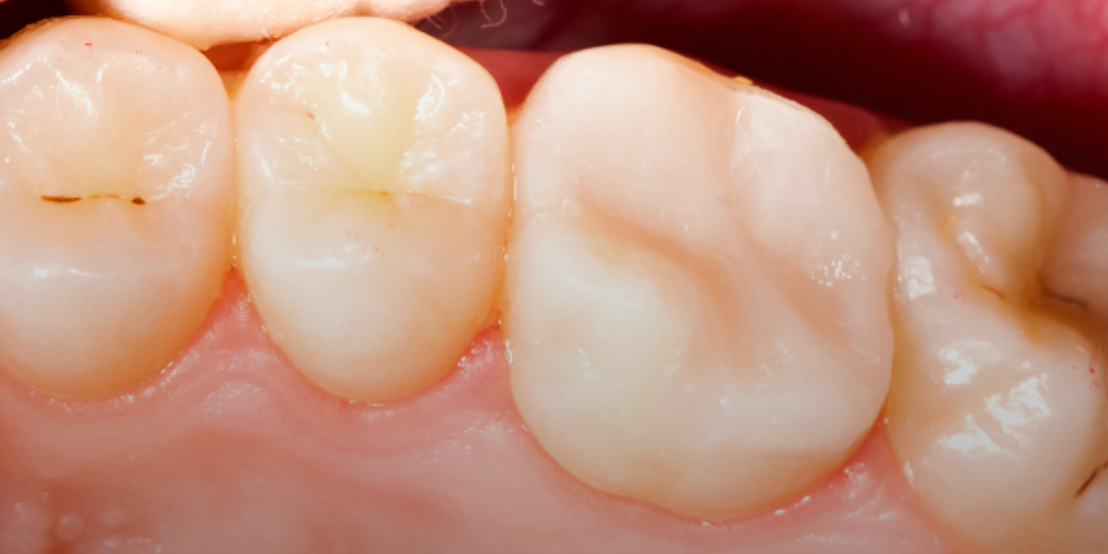

Root canal therapy removes infected pulp while preserving the natural tooth, offering pain relief and preventing further issues. At our clinic, we perform root canal Dubai procedures using advanced tools for accurate cleaning and long-term results.

In cases of severe pain, we offer emergency root canal Dubai services to treat infections promptly. Our team follows proven root canal treatment steps in Dubai to ensure your comfort and a smooth recovery. A crown is placed afterward to restore function and protect your natural smile.

Our modern root canal Dubai is designed to relieve discomfort while preserving your natural tooth. Using advanced technology and a gentle root canal treatment steps Dubai, we effectively remove infection and seal the area to ensure long-term strength and protection. This treatment restores function and comfort with minimal downtime, helping you maintain a healthy, confident smile. +97145641222